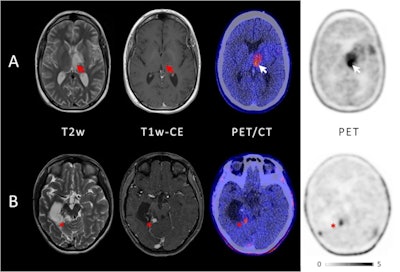

Example of two patients with concordant imaging results (A) and incremental diagnostic value of F-18 FET-PET (B). (A) Example of a patient with an anaplastic astrocytoma WHO grade III who was treated with combined radiochemotherapy prior to PET. Axial T2-weighted imaging and T1-weighted imaging with contrast enhancement depict the tumor in the left thalamus and insular region (red arrows); axial PET shows high uptake of F-18 FET in these regions (white arrows). Both MRI and PET correctly identified the tumor recurrence. (B) Example of a patient with a pilocytic astrocytoma who was treated with surgery and chemotherapy prior to PET. Axial T2-weighted imaging and T1-weighted imaging with contrast enhancement show cystic as well as contrast-enhancing lesions next to the surgical cavity consistent with both unspecific changes and tumor recurrence (red asterisk); in contrast, axial PET demonstrates focal high uptake of F-18 FET (white asterisk). Image courtesy of the European Journal of Nuclear Medicine and Molecular Imaging through CC BY 4.0.Fourteen out of the 21 patients showed positive uptake of the FET radiotracer by tumors: three out of five with newly diagnosed brain tumors and 11 out of 16 with previously treated lesions. In these patients, FET-PET had an impact on further treatment decisions, the researchers found.